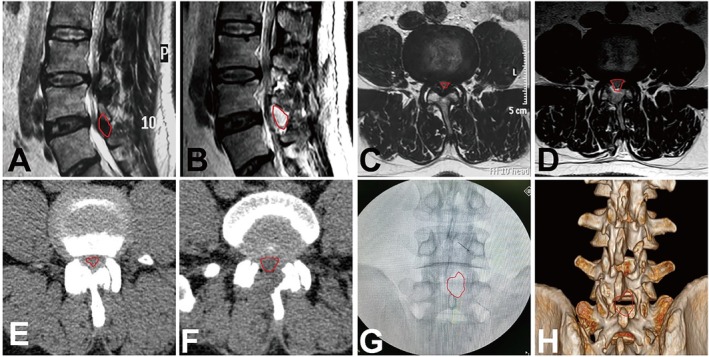

Methods: Between August 1, 2018, and December 1, 2020, a total of 316 consecutive cases underwent endoscopic decompression for LSS following conservative treatment. Based on specific selection criteria, 176 of these cases were retrospectively included in this study. The minimally invasive decompression was performed using a percutaneous uniportal and lateral interlaminar endoscopic approach under local anesthesia. This endoscopic procedure involved comprehensive decompression of the central canal and unilateral recess, addressing the lamina, hypertrophic ligamentum flavum (LF), and medial osteophytes of the facet joint. Clinical outcomes were assessed using the single continuous walking distance (SCWD) without pain, the modified MacNab criteria, the Oswestry Disability Index (ODI), and the visual analogue scale (VAS). Radiographic changes, both preoperative and postoperative, were documented and analyzed. This analysis included evaluating the stability of the lumbar spine through lumbar hyper-flexion and hyper-extension X-rays, as well as determining the lumbar canal cross-sectional area (CCA) using CT scans.

Results: The mean follow-up period was 47.4 ± 7.1 months. The average operative duration was 65.3 ± 12.6 min, and the mean estimated blood loss was 10.4 ± 8.5 mL. The average length of postoperative hospital stay was 2.2 ± 1.3 days. There was a significant improvement in SCWD without pain (p < 0.05). Postoperatively, the ODI and VAS scores for both back and leg pain showed significant reductions (p < 0.05). Based on the modified MacNab criteria, the overall rate of good-to-excellent outcomes was 95.45%. The CCA increased significantly from 52.0 ± 11.0 to 122.5 ± 12.1 mm2 (p < 0.05). The stability of the spine did not exhibit significant changes compared to the preoperative state.